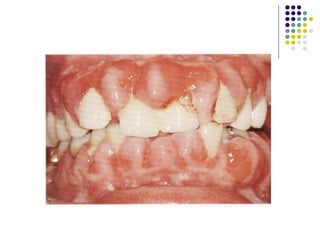

PRINCIPALES ENFERMEDADES PERIODONTALES  ASOCIADAS A PLACA BACTERIANA. GINGIVITIS Inflamación del tejido de la encía en su margen gingival.  No involucra los tejidos de soporte del diente. La gravedad depende de la intensidad, duración y frecuencia .

Signos y síntomas: Encía eritematosa (roja). Sangrado provocado por estimulo. Edema (encía hinchada). Perdida del punteado. Halitosis. Tratamiento y pronostico: Eliminar el origen, placa bacteriana y calculo. Buena higiene oral.

Signos y síntomas:Encía eritematosa (roja). Sangrado provocado por estimulo. Edema (encía hinchada). Perdida del punteado. Halitosis. Tratamiento y pronostico: Eliminar el origen, placa bacteriana y calculo. Buena higiene oral.